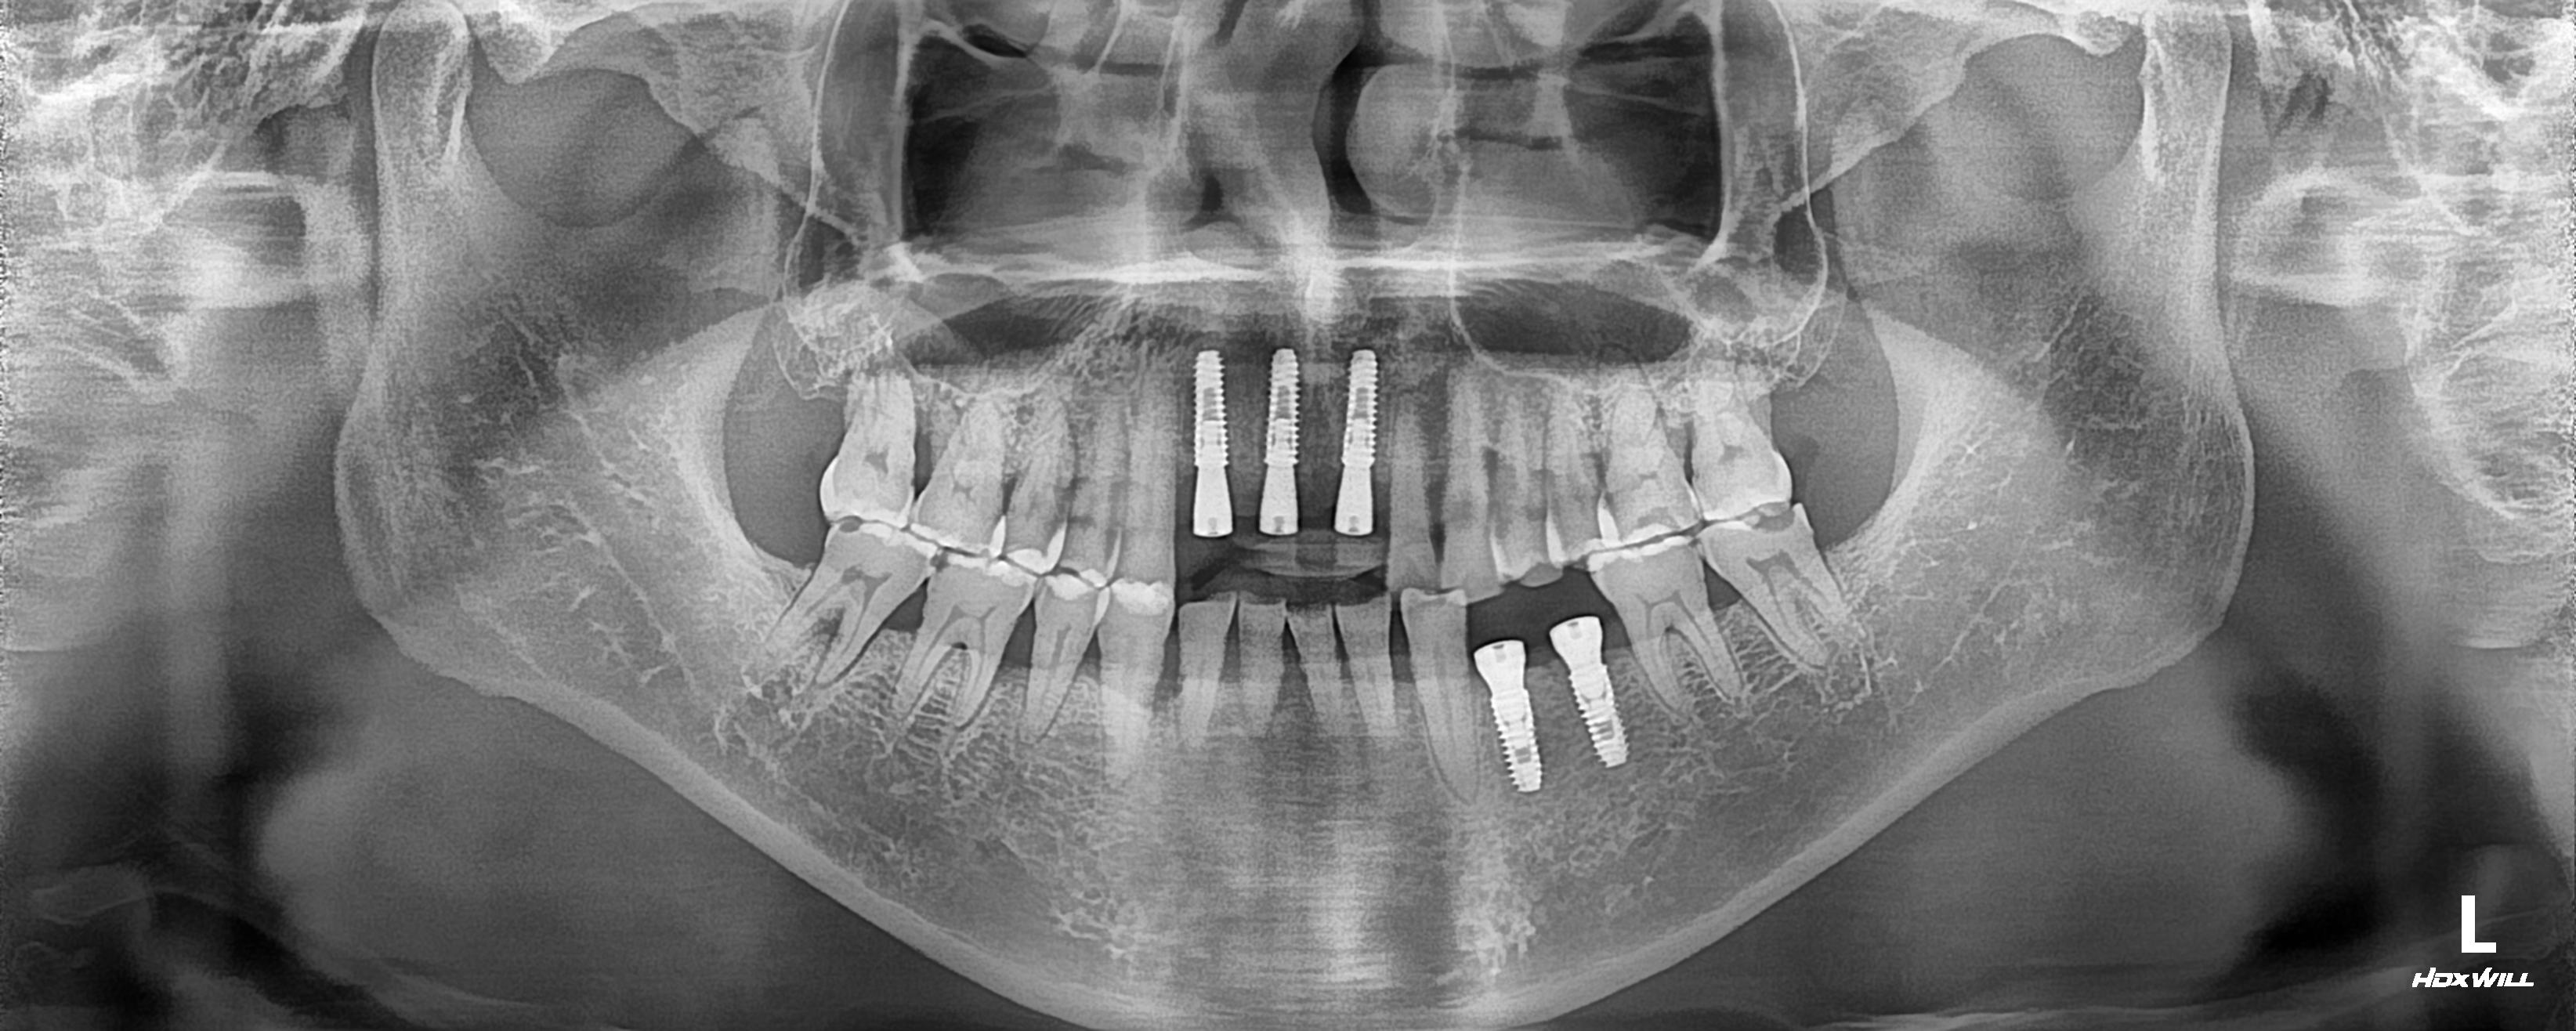

네비게이션 수술 전

네비게이션 수술 후

[임플란트] 네비게이션 임플란트 수술 케이스

"잇몸 절개가 적고 통증이 적은 네비게이션 수술을 받고 싶어요" 최…

네비게이션 수술 전 네비게이션 수술 후

"잇몸 절개가 적고 통증이 적은 네비게이션 수술을 받고 싶어요"

최근 컴퓨터 분석툴을 이용한 네비게이션 임플란트 수술에 대해 관심이 많아지고 있습니다.

네비게이션의 경우 짧은 수술 시간과 잇몸절개를 최소화 하여 수술 후 부작용이 적은 장점이 있습니다.

이 환자분도 앞니와 왼쪽 아래 어금니 부위 치주염으로 발치를 시행하고 네비게이션 임플란트 수술을 진행하였습니다.

수술 후 치과에 대한 공포와 통증에 대한 두려움이 최소화 되는 네비게이션 임플란트 수술이 치과를 무서워 하는 환자분들에게 많은 힘이 될 것이라 생각됩니다. ^^